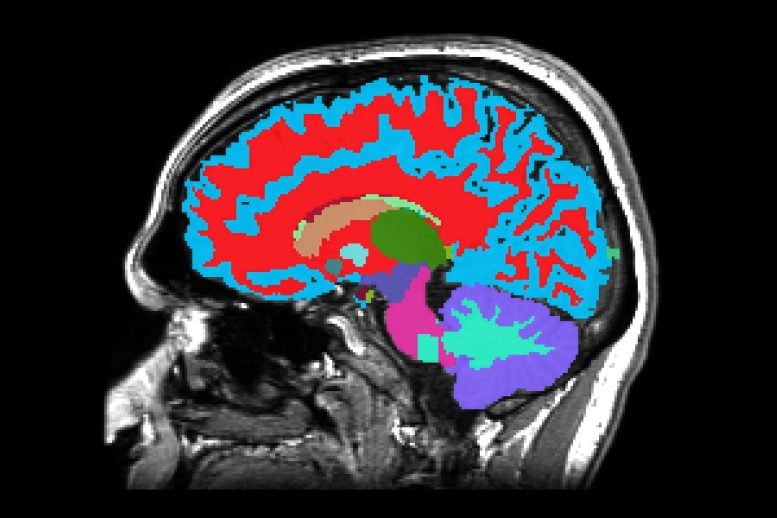

Researchers have created a brand new software that reads how briskly you’re ageing, utilizing only one mind scan. The scan can spot indicators of future illnesses like dementia earlier than signs seem. Folks ageing quicker had weaker reminiscence, extra well being issues, and even a better danger of early loss of life. The software works throughout totally different nations and backgrounds, […]